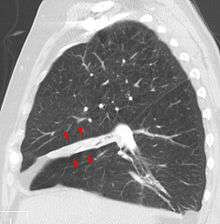

Atelectasis of a person's right lung | |

- chest X-ray

Post-surgical atelectasis will be bibasal in pattern.